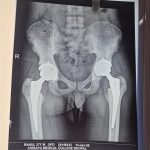

- Robotic Joint Replacement

- Hip Replacement Surgery